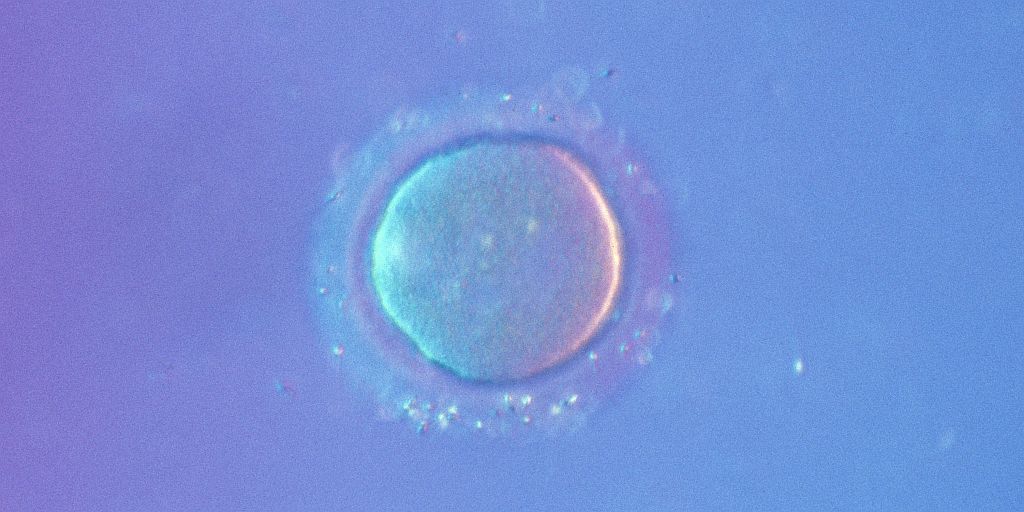

Sie sind nur 0,11 bis 0,14 Millimeter groß und doch entsteht aus ihnen alles menschliche Leben: Eizellen. Zum Zeitpunkt ihrer Geburt verfügen Mädchen über ein bis zwei Millionen unreife Eizellen, nach den Wechseljahren sind noch um die 1.000 in den Eierstöcken. Zwischen 20 und 30 ist die Fruchtbarkeit einer Frau statistisch gesehen am höchsten. Frauen in diesem Alter sind die perfekten Eizellspenderinnen. Und ein paar von diesen tausenden Zellen an Frauen abzugeben, die zu alt für eine Schwangerschaft oder unfruchtbar sind, dürfte doch eigentlich kein Problem sein, oder?